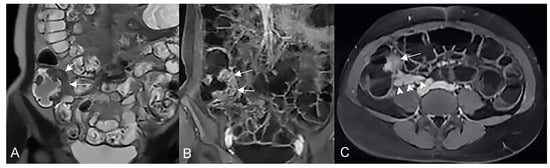

Figure 9.

Pathological junctions of intestinal segments through enteroenteric fistulas, which represents internal fistulas that connect intestinal segments such as ileo-sigmoidal (A) and ileo-colic (B).

Figure 10.

Axial (A) and coronal (B,C) contrast-enhanced fat-suppressed T1-weighted images and axial FIESTA image (E) of the same patient show a complex fistula formed by the intersection of multiple fistulous arms that connect pathological segments of the small intestine to each other and to the ascending colon through the mesentery. These fistulous pathways, intersecting each other, end up taking on the starry appearance, typical of complex fistulas (D).